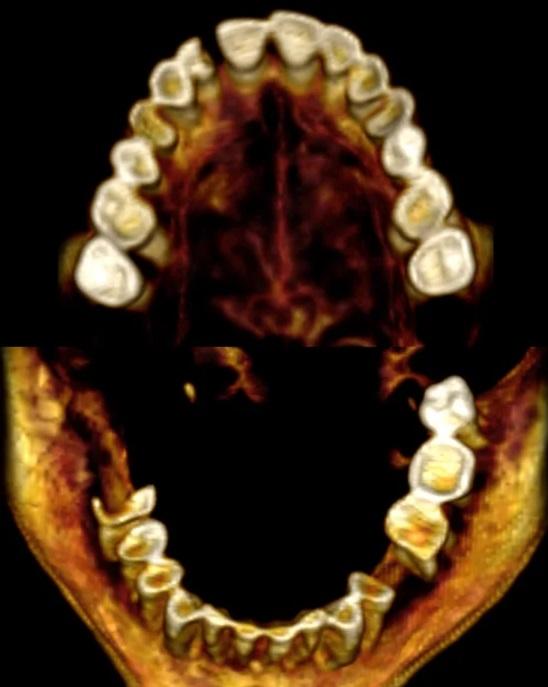

科學家藉由電腦斷層掃描(CT scan)對「尖叫女子」木乃伊進行虛擬解剖後推測,她可能在極度痛苦中離世,並在死亡時經歷一種罕見的肌肉僵硬,稱為「屍體痙攣」(cadaveric spasm)。

領導研究的埃及開羅大學放射學教授薩利姆(Sahar Saleem)解釋,屍體痙攣會在身體或精神承受劇烈痛苦後發生,收縮的肌肉在死後立刻變得僵硬。研究發現,「尖叫女子」過世時年約48歲,患輕度脊椎關節炎,已失掉部分牙齒。遺體大約在3,500年前經過防腐處理,那時是古埃及「新王國時期」(New Kingdom)。